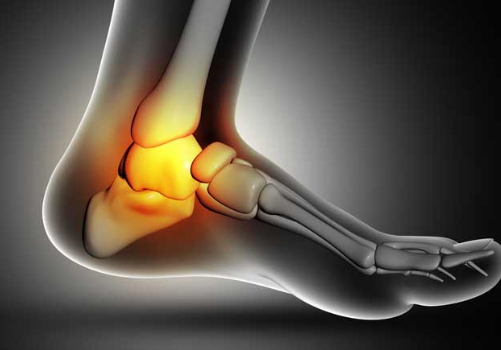

2. 관절염과 관절 염증

관절염은 관절의 염증을 포함하는 상태입니다. 이는 발목을 포함한 몸의 어떤 관절이든 영향을 미칠 수 있습니다. 발목에서 볼 수 있는 두 가지 일반적인 관절염 유형은 다음과 같습니다:

골관절염 (Osteoarthritis)

골관절염은 주로 나이가 들면서 연골이 점차 붕괴되는 과정과 관련이 있습니다. 발목에서는 연골이 파괴되면서 통증, 경직 및 기동성 감소가 발생할 수 있습니다.